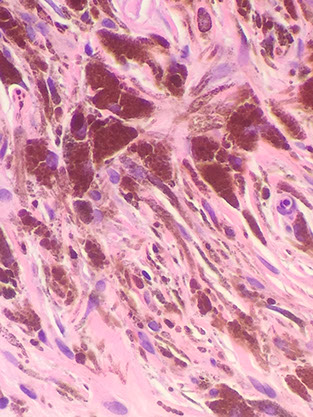

• Metastatic Melanoma

Melanoma

Incidence on the rise; ~10k deaths annually

- MCC death from cutaneous neoplasm

Common tumor w high risk of mets; may or may not be assoc c inc sun exposure

Dysplastic nevus (atypical mole) is a precursor lesion

*** ABCDEF: Asymetry, Borders irregular, Colors (multicolored), Diameter (larger [>0.6 cm]), Evolution / Enlargment (and Elevation), Fair skin people ***

Micro: asymmetric, large DEJ nests (>10 cells), pagetoid growth, atypia, mits deep in the tissue

- can also see inflam (lichenoid or chronic), pigment incontinence, cells c whispy brown cytoplasm

- lymphs act like riot police trying to hold back an angry mob (vs the Cocktail Party of a halo nevus)

IHC: (+) S100 (>99.7% [+]), PNL2, Melan-A, HMB45/50 (stains superficial and deep cells, vs nevi which stain only superficial cells), KBA62, MITF, vimentin, high Ki67